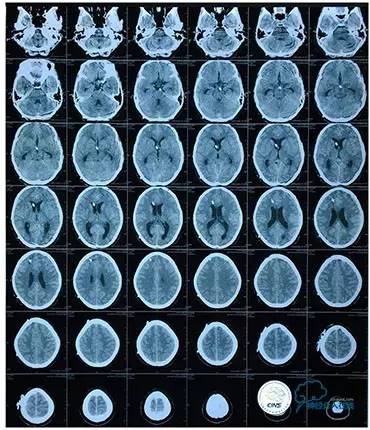

头颅CT

MRI T1

MRI T2

MRV